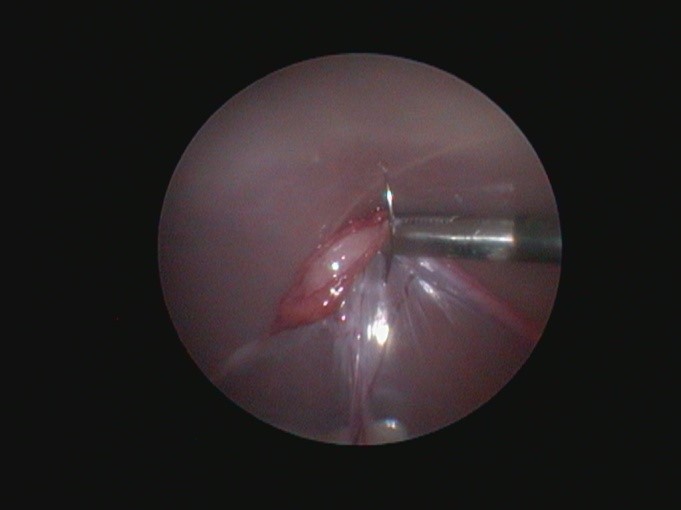

Во время операции «глазами» хирурга является специальная камера- лапароскоп, диаметр которой, обычно, от 3 до 10 мм. Данной камерой хирург имеет возможность не только контролировать ход операции под увеличением, но и есть возможность осмотра других органов брюшной полости (почки, печень, селезенка, мочевой пузырь) на наличие каких-либо видимых отклонений, что невозможно сделать полноценно при проведении стерилизации «открытым» способом

Так же, проведение операции под четким контролем лапароскопа позволяет снизить возможность неполного удаления ткани яичника, что может привести к возникновению симптомов течки в дальнейшем. - При удалении яичников не накладывается лигатура, а проводится коагуляция связки яичника специальным биполярным инструментом, без использования шовного материала. При использовании этой техники исключены реакции на шовный материал.